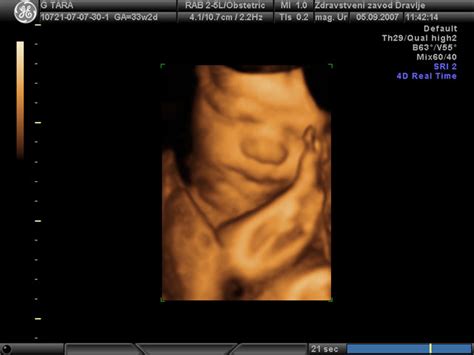

- Ultrazvočni pregledi: Omogočajo natančno določitev pričakovanega termina poroda že med 11. in 14. tednom nosečnosti, ter spremljanje rasti in razvoja ploda skozi celotno nosečnost. V primerih, ko plod zaostaja v rasti, kot je bilo to v izkušnji mlade nosečnice, ki je zanosila kmalu po srednji šoli, so redni ultrazvočni pregledi ključni za oceno stanja in pravočasno ukrepanje.